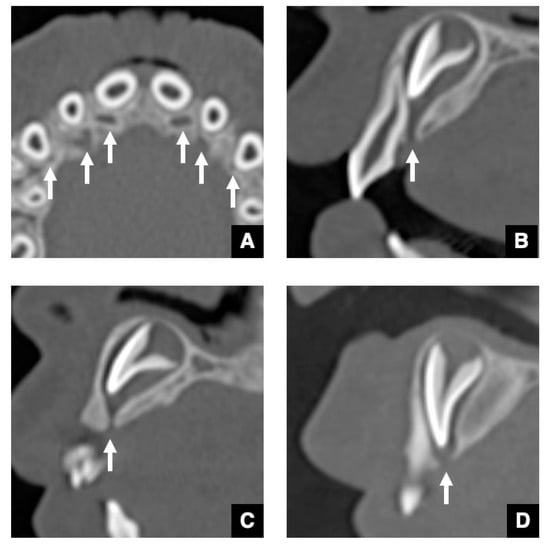

2.2. CT Images of GT in Accessional Tooth